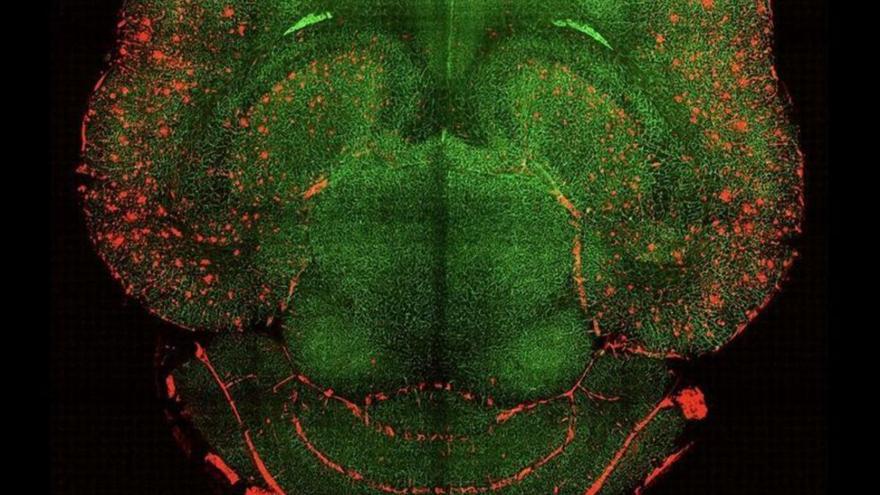

Imatge del cervell d’un dels ratolins tractats amb injeccions de nanopartícules. | IBEC

Aquesta teràpia es va aplicar en ratolins de 12 mesos, l’equivalent a 60 anys en humans, amb símptomes d’Alzheimer. En hores es van començar a veure canvis al seu cervell i dies més tard ja es van veure canvis positius en el seu comportament i memòria. Sis mesos després, quan els animals tenien el cervell d’un nonagenari, ja no mostraven símptomes de la malaltia, sinó que es comportaven com a exemplars completament sans.